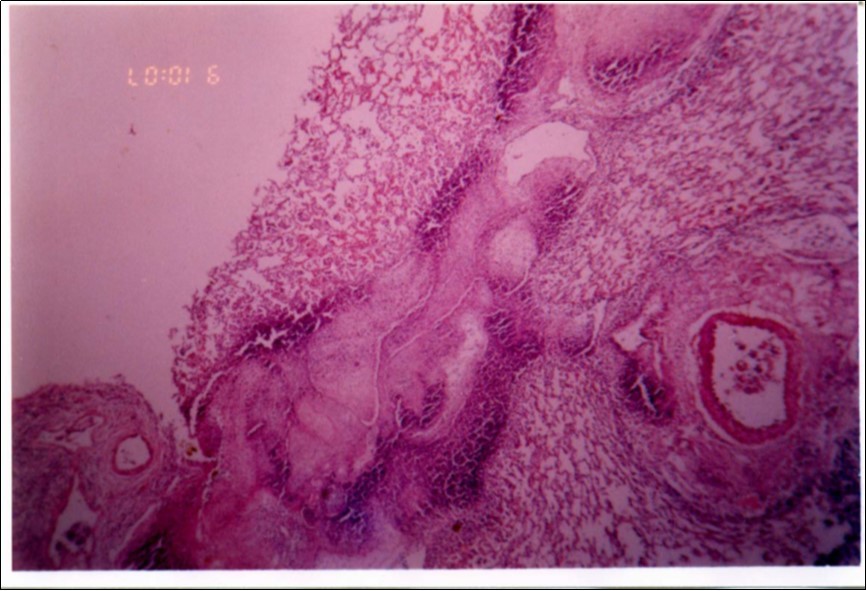

Figure 3, Figure 4 and Figure 5 show different histopathological pictures of hepatized lung tissue samples from which Mmm isolates were recovered. In Figure 3, widened interlobular septa, due to presence of fibrinous necrosis and cellular infiltration were observed. Figure 4 shows extensive loss of airspace due to necrosis and infiltration of neutrophils. Figure 5 shows hyperemia of alveolar wall capillaries and infiltration of few fibrin and neutrophils.

Figure 3.Widened interlobular septa in pneumonic lung tissue (H&E ×200).

Although no advanced techniques like PCR were used to identify the isolates, procedures used in this study were quite enough to confirm the incidence. Affected animals with CBPP were diagnosed based on the clinical signs, the PM findings, the typical histopathological picture in addition to the isolation of the causative agent and its subsequent identification using cultural and biochemical procedures. Identification of the isolates was confirmed by the growth inhibition test as recommended in OIE manual 10. The histopathological sections of diseased lungs, from which Mmm (SC) was isolated, showed typical histopathological picture of CBPP. The CBPP lesion comprises abronchiolar necrosis and oedema which progress rapidly to an exudative serofibrinous bronchiolitis with extension to the alveoli and uptake of alveolar fluid into tissue spaces 17, lymphatic vessels and ultimately septal lymphatics 18. With stasis, lymphatic vessels become thrombosed and ultimately fibrosed 19. The histological section of the lung in acute stage of the disease showed odema in the lymphatics of the interlobular septa and interstitial tissue and massive infiltration of fibrin, macrophage and neutrophils into the alveolar lumen 20. Also there was presence of lymphocytes and alveolar macrophages around the lymphatic vessels and septa margin 21. These findings supported the isolation results and gave additional evidence for the diagnosis of the disease.